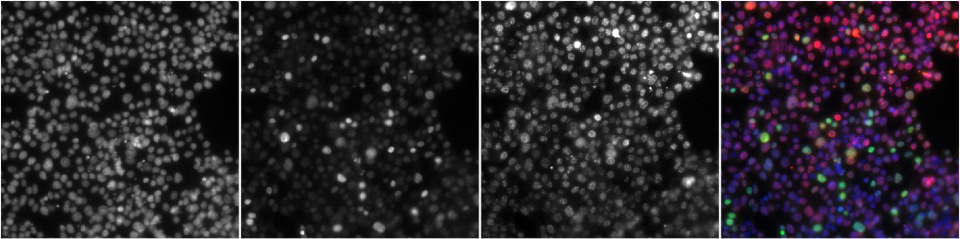

High Content Screening (HCS) is an advanced laboratory technology used to help identify changes in cellular phenotypes (i.e. visual or structural alterations) at the single‑cell level.

It combines fluorescent staining, automated microscopy, and software image analysis.

By simultaneously staining multiple protein targets (called epitopes) within each cell, HCS provides us with valuable insights into various cellular pathways activated by representative extracts generated either from our next generation products (NGP), or neat liquids/constituents – and allows us to compare the results against cigarette smoke.

As this approach captures numerous parameters across thousands of cells, it generates a very large amount of data per experiment – hence ‘High Content Screening’.